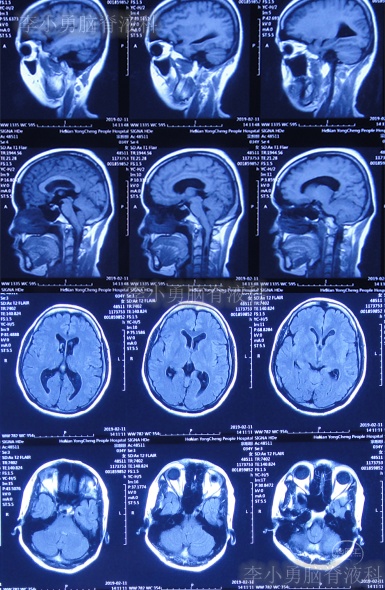

患者2019年2月初,因数次出现发作性黑蒙,2019年2月10日就诊于当地的河南省永城市某医院,查头颅CT未见明显异常(图-1);次日再查头颅核磁、颈椎核磁(图-2、图-3)后发现小脑扁桃体下疝畸形合并脊髓空洞。

图-2:2019年2月12日头颅核磁

图-3:2019年2月13日头颅核磁